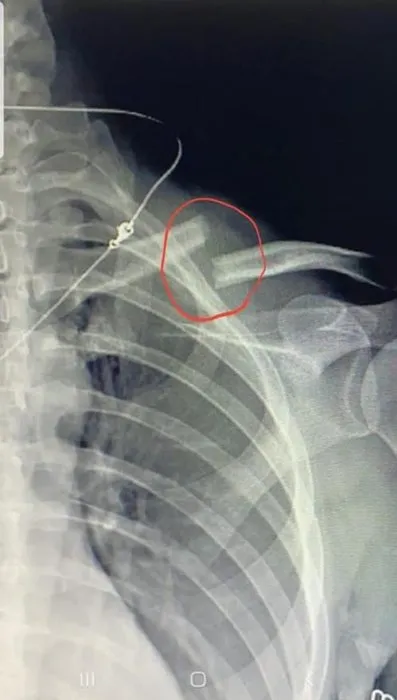

Eli yüzü kan içinde kalan kadın, gürültüyü duyarak gelen komşusu ve eski eşinin yardımıyla hastaneye götürüldü. Tedavi altına alınan Chikareva'nın köprücük kemiğinin kırıldığı belirlendi. Tedavisi tamamlanan Chikareva, darp raporu alarak eşinden şikayetçi oldu. Gözaltına alınan Salih G., çıkarıldığı mahkemece serbest bırakıldı.